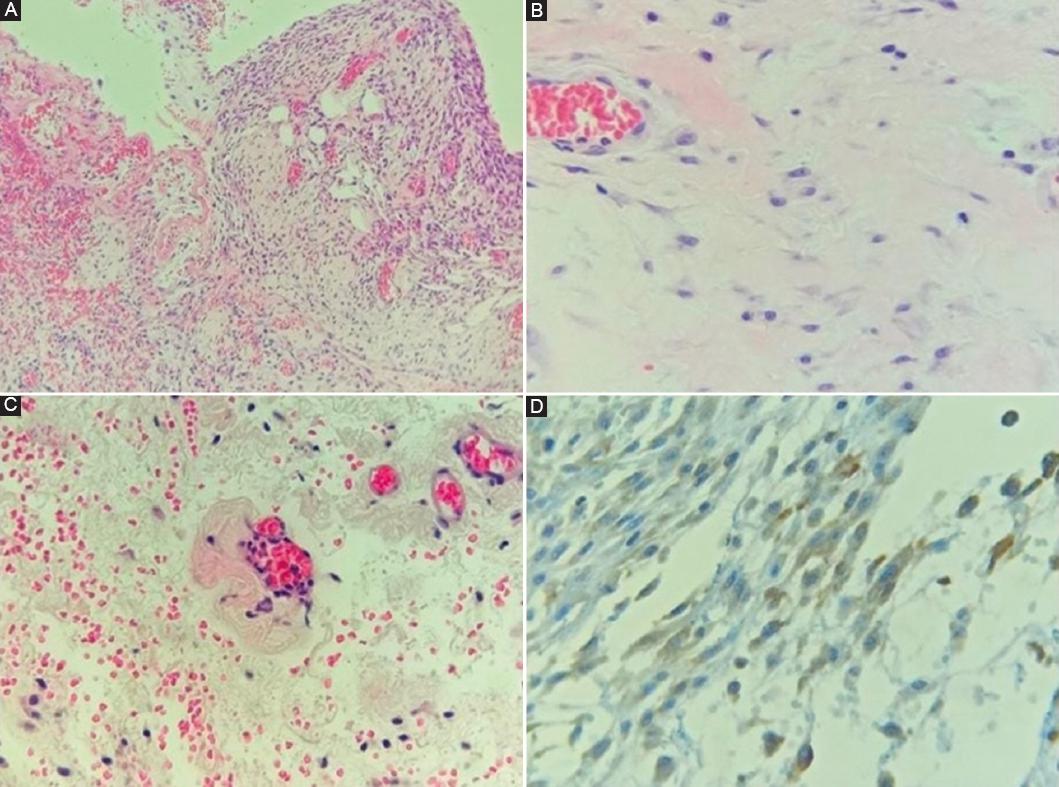

Histológicamente se observó engrosamiento de la membrana peritoneal conformado por matriz fibrosa, con células similares a fibroblastos, y abundantes vasos sanguíneos con variación en el grosor de su pared y congestivos. La capa de células mesoteliales era discontinua. Todos los fragmentos se encontraron recubiertos por material de aspecto fibrinoso. Las células fusiformes resultaron positivas para D2-40. Hallazgos microscópicos compatibles con esclerosis peritoneal encapsulante (Fig. 3).

Figura 3 A: tinción de hematoxilina y eosina, 10×. Cubierta mesotelial discontinua y de grosor variable. En la izquierda de la imagen se observa recubrimiento por material fibrinoso. B: tinción de hematoxilina y eosina, 40×. Células fusiformes similares a fibroblastos. Los núcleos con cromatina granular fina y hasta tres nucléolos pequeños. C: tinción de hematoxilina y eosina, 40×. Las paredes de los capilares con acentuada variación en su grosor. D: tinción de inmunohistoquímica para D2-40, 40×. Células fusiformes positivas.

Braun et al.8 propusieron las siguientes características histológicas para diagnosticar esclerosis peritoneal encapsulante histológicamente: presencia de células similares a fibroblastos, presencia de exudado, denudación de células mesoteliales, zonas acelulares, densidad de los vasos sanguíneos, variación de la pared de los vasos sanguíneos, presencia de infiltrado inflamatorio agudo y crónico, depósitos de fibrina, depósitos de hierro y expresión de podoplanina (D2-40) en células vasculares y no vasculares. De estas, la presencia de células similares a fibroblastos, la denudación de células mesoteliales y la expresión de podoplanina son las más frecuentes en los pacientes con esclerosis peritoneal encapsulante.